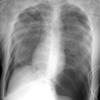

Gallery Blunt Chest Trauma Pneumothorax

Pneumothorax